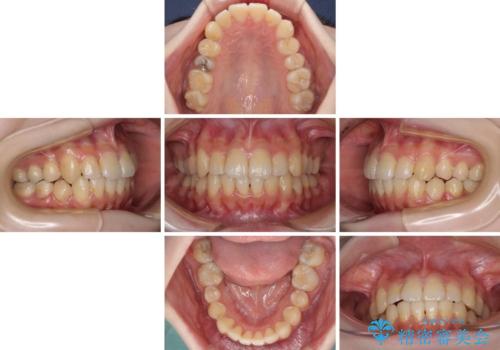

デコボコ歯列をきれいに インビザラインによる矯正治療

- 上下歯列全体のデコボコを気にして来院された患者様です。

主に下顎歯列全体の後方移動とIPR(歯と歯の間を削る)によってデコボコが解消するように設計し、インビザラインにより治療を行うこととしました。

奥歯の知覚過敏が顕著となり、その影響で奥歯の咬み合わせ改善のための顎間ゴムの装着ができず、咬合を仕上げるまでに長い期間を要することとなりました。